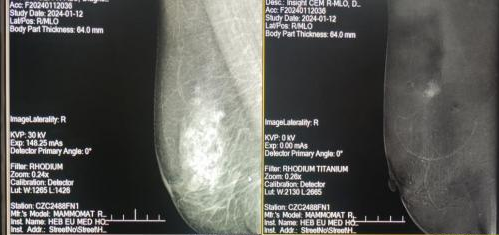

2024年1月12日,新年伊始,河北工程大学附属医院影像科成功开展邯郸市首例对比增强双能数字化乳腺X线摄影(CEDM)检查技术。该检查的成功开展,填补了邯郸市对比增强双能数字化乳腺X线摄影(CEDM)检查技术的空白,为广大女性提供了更多的乳腺疾病检查手段。

3.对比增强双能数字化乳腺X线摄影(CEDM)检查技术:在乳腺X线照片中,钙化点通常是对癌症做出早期诊断的重要线索。若钙化点与乳腺的软组织区别不大,则有可能被漏掉,尤其是致密型乳腺和经过手术或放疗后的乳腺,由于缺乏自然对比,对于某些病变则难以显示。在此背景下,针对常规乳腺X线摄影的不足,CEDM检查技术应运而生,也是近年来全数字化乳腺X线摄影技术的新进展之一。该技术是注射对比剂后拍摄双乳MLO位和CC位高、低能量图像,将增强前后低能和高能图像相减获得双能减影影像,通过观测病变血流供应与正常乳腺组织的差异,发现常规乳腺X线摄影上难以显示的病灶,特别是在致密型乳腺中,利用双能成像技术,病灶显示更加清晰,可显著提高诊断准确率。